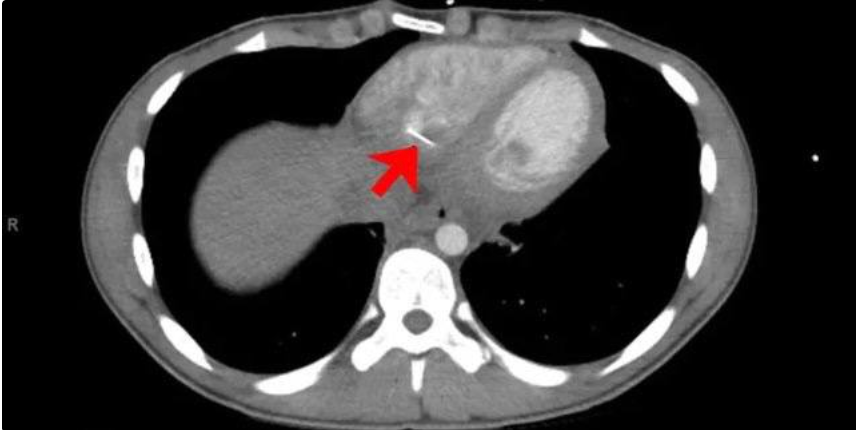

Медики повезли подростка на томографию, где выяснилось, что в сердце застряло инородное тело около 3,5 сантиметров в длину. Юноша признался, что сам себе шьет вещи и когда он в очередной раз держал во рту булавку, нечаянно ее проглотил. Во время операции хирурги подтвердили, что это была действительно булавка.

Специалисты считают, что игла попала в сердце напрямую из желудка или из пищевода.